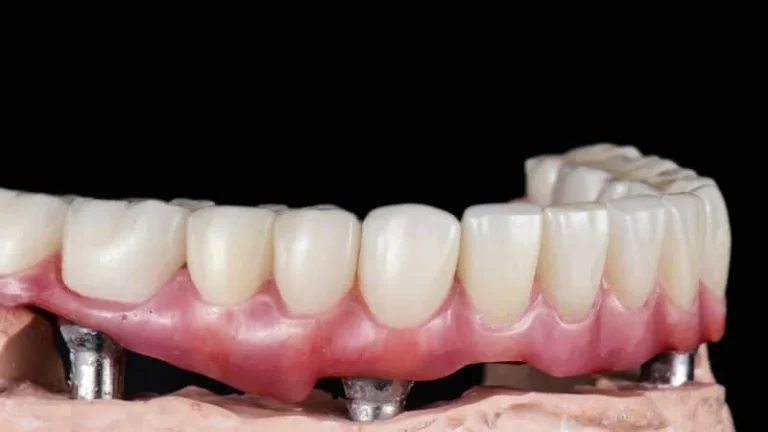

Dai singoli impianti alle riabilitazioni complete del cavo orale, Dentale Albania è la destinazione ideale per una trasformazione dentale in Albania.

Riparare denti danneggiati o sostituire quelli mancanti.